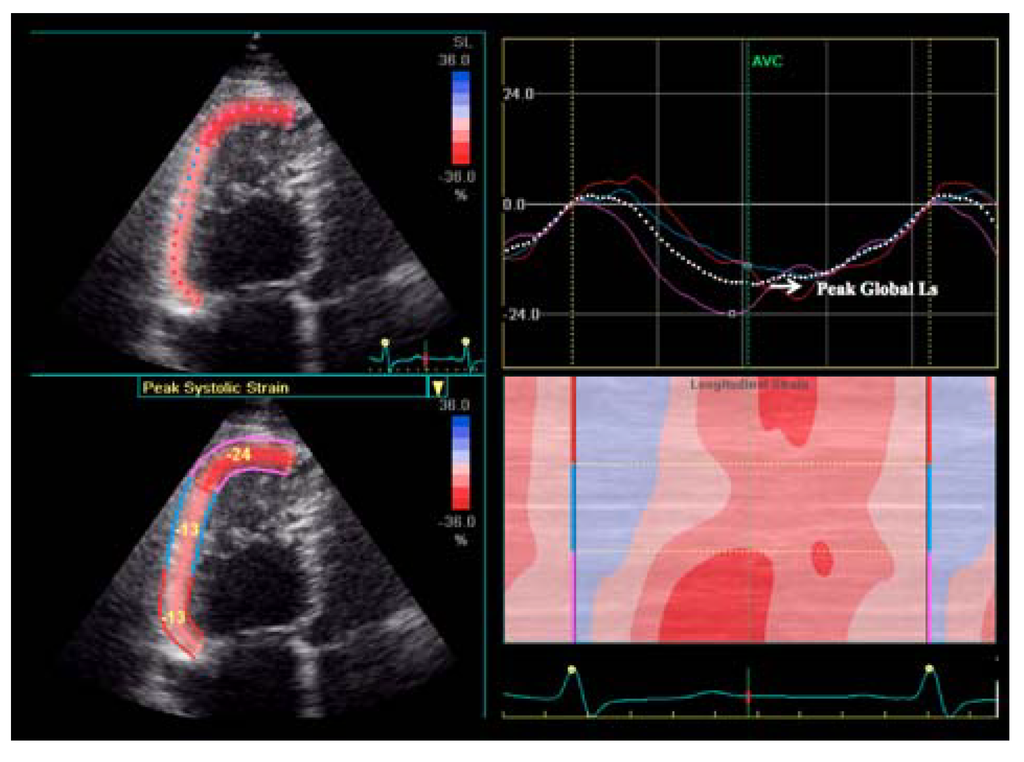

RV longitudinal strain assessed by STE strain imaging is significantly impaired in patients with PH (Figure 2) and it is inversely correlated with systolic pulmonary artery pressure and RV dimensions [,,,,].

Figure 2.

Right ventricular longitudinal strain impairment in pulmonary hypertension patient. Ls = longitudinal strain.

RV longitudinal strain values demonstrated a significant prognostic role in PH which was incremental to clinical status, overcoming the other echocardiographic parameters [,,]. RV longitudinal strain has been reported to be a predictor of cardiovascular events [], all-cause mortality and complications []. Moreover, Fine et al. [] demonstrated that abnormal RV strain is predictive of reduced survival, stratifying patients prognosis.